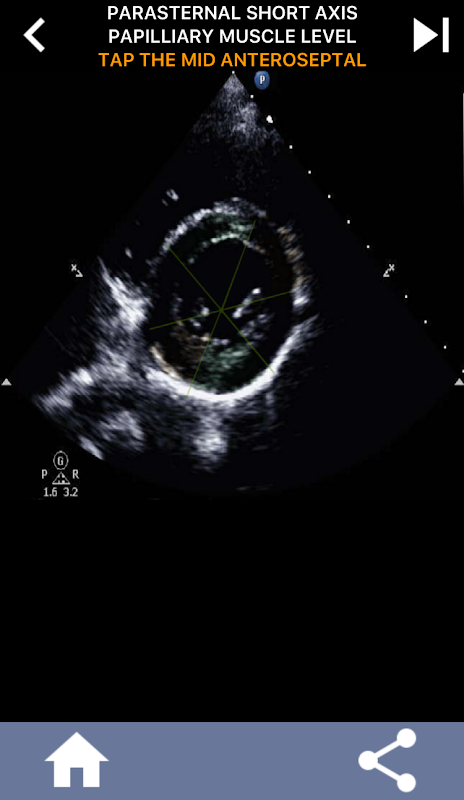

Abordagem visual baseada em questionário para aprender os segmentos cardíacos da AHA: ecocardiografia

Este aplicativo testará seu conhecimento usando imagens de eco reais, que geralmente considero o melhor método de ensino.